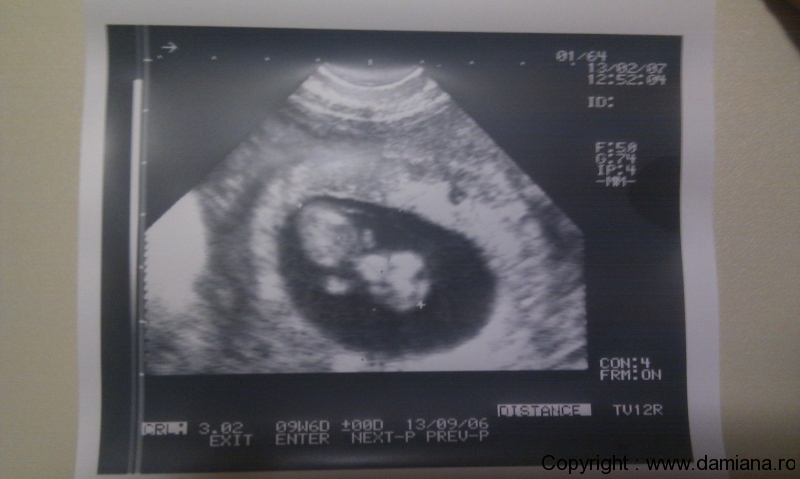

Aceste ecografii sunt facute cand micutii aveau doar 10 saptamani . Unu masoara 3,06 cm , altul 2,70 cm. Sa speram ca cel mare e baietel si micuta – fata 🙂